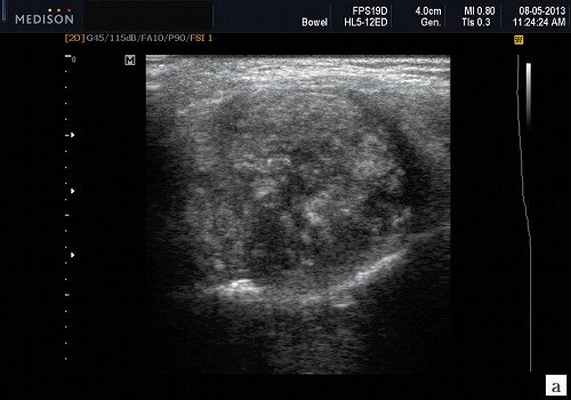

- обструктивные сиаладениты, развивающиеся при затруднении оттока слюны при обструкции выводного протока камнем (рис. 5-7) или сгустившимся секретом, а также вследствие рубцового стеноза протока. По распространенности процесса различают очаговый, диффузный сиаладениты и сиалодохит - воспаление выводного протока. Течение процесса может быть острым и хроническим;

Рис. 5. Камень протока поднижнечелюстной слюнной железы.

Рис. 6. Камень в паренхиме поднижнечелюстной слюнной железы.

Рис. 7. Камень в протоке поднижнечелюстной слюнной железы.